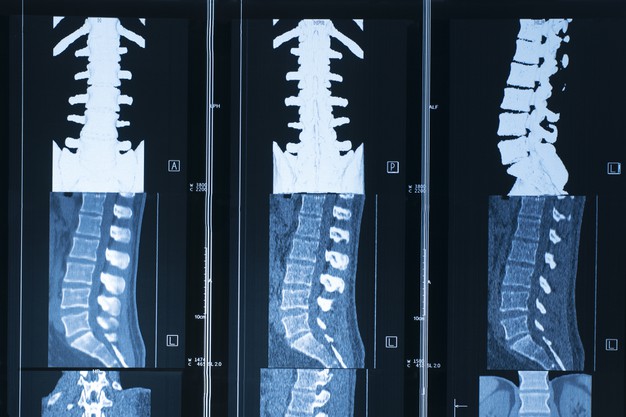

Raio X Da Coluna Lombar Com Hérnia De Disco

Raio x da coluna lombar com hérnia de disco. O raio-X da coluna tem algumas utilidades como neste caso descartar outras causas de dor nas costas. Estenose lombar da coluna vertebral. Estatística das Hérnias Discais 15 da população mundial sofre.

Testes de imagem gerais para hérnia de disco. Na maioria dos casos os sintomas melhoram naturalmente com três meses mas podem ser auxiliados com tratamentos clínicos e fisioterapêuticos. Mas é a ressonância magnética RM o exame de imagem mais.

O raio X da coluna é um exame que serve para avaliar as seguintes estruturas anatómicas. Hérnia de disco - Aprenda sobre causas sintomas. A dor pode ser sentida ao longo do caminho do nervo comprimido pela hérnia de disco.

A coluna vertebral conhecida como espinha é formada por 32 ossos que são chamados de vértebras e 23 discos que se localizam entre as vértebras. O médico ainda pode solicitar exames de imagem para ajudar a diagnosticar sua condição.

O raio X da coluna é um exame que serve para avaliar as seguintes estruturas anatómicas. O raio X da coluna é um exame que serve para avaliar as seguintes estruturas anatómicas. Cerca de 80 das pessoas irão sentir a dor lombar em algum momento de suas vidas. A dor pode ser sentida ao longo do caminho do nervo comprimido pela hérnia de disco. Indicações do RX da coluna. Computadorizada TC que antigamente era chamada. Na maioria dos casos os sintomas melhoram naturalmente com três meses mas podem ser auxiliados com tratamentos clínicos e fisioterapêuticos.